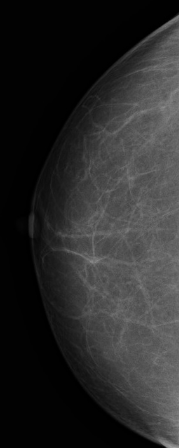

유방암 검사 비용은 보통 유방촬영(영산 진단)과 유방초음파(초음파 진료) 두 가지입니다.

검사할 때 건강보험 혜택이 적용되는 기준은 따로 있습니다. 우선 가장 보편적으로 사용하는 흑백 영상 초음파 장비는 건강보험이 적용됩니다. 단, 진단 결과에 따라서 양성이냐 악성이냐 여부에 따라 최종 결정됩니다.